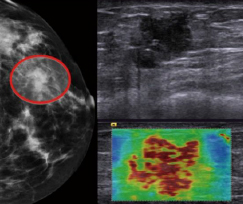

超音波画像診断装置は,X線による被ばくがないこともあり,特に乳腺の多い20代,30代や妊婦にも安心して受けられることが特長。これまでの検査では,乳腺内の組織の形や血流情報を診るのが一般的であったが,「ACUSON S Family HELX Evolution」は,しこりの形状や血流情報だけでなく,「硬さ」を画像化・数値化することができる「アーフィーイメージング技術*1」及び「シアウェーブ エラストグラフィ技術*2」を搭載しており,これらを併用することで,さらに精度の高い診断と経過観察に貢献する。つまり,これまで触診に頼っていたしこりの硬さを画像化・数値化できるようになり,より客観的で普遍的な検査が行えるようになる。また,受診者が体位を変えることなく瞬時に検査ができるため,受診者の身体的・精神的な負担も少なくなる。さらに,検診で乳がんを疑われた場合,一般的には細胞の一部を採取して行う病理検査で確定診断を行うが,「硬さ」の情報が加わることにより,不要な病理検査を減らせることも期待できる。

臨床画像 |

*1: アーフィーイメージング技術: 超音波の力で組織を押し,その変位(位置の変化)を画像化・数値化することで,硬さを評価する技術

*2: シアウェーブ エラストグラフィ技術:超音波の力で組織を押してせん断弾性波(シアウェーブ)を発生させ,組織内部を伝搬する速度で硬さを測定,数値化する技術